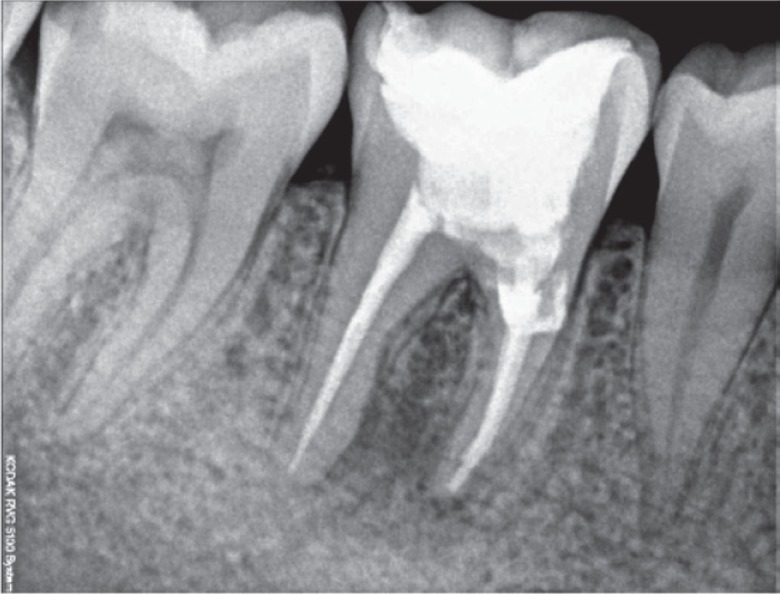

Figure 1). Radiographic analysis revealed a periapical radiolucent lesion around the mesial and distal root of tooth #46, and the periradicular dentin at the coronal third of the mesial root was compromised as a result of the poor endodontic access cavity (

Figure 2).

Figure 2Preoperative radiograph revealing a periapical radiolucent lesion in the region of the mesial and distal root of tooth #46, as well as compromised periradicular dentin at the coronal third of the mesial root due to a poor endodontic access cavity.